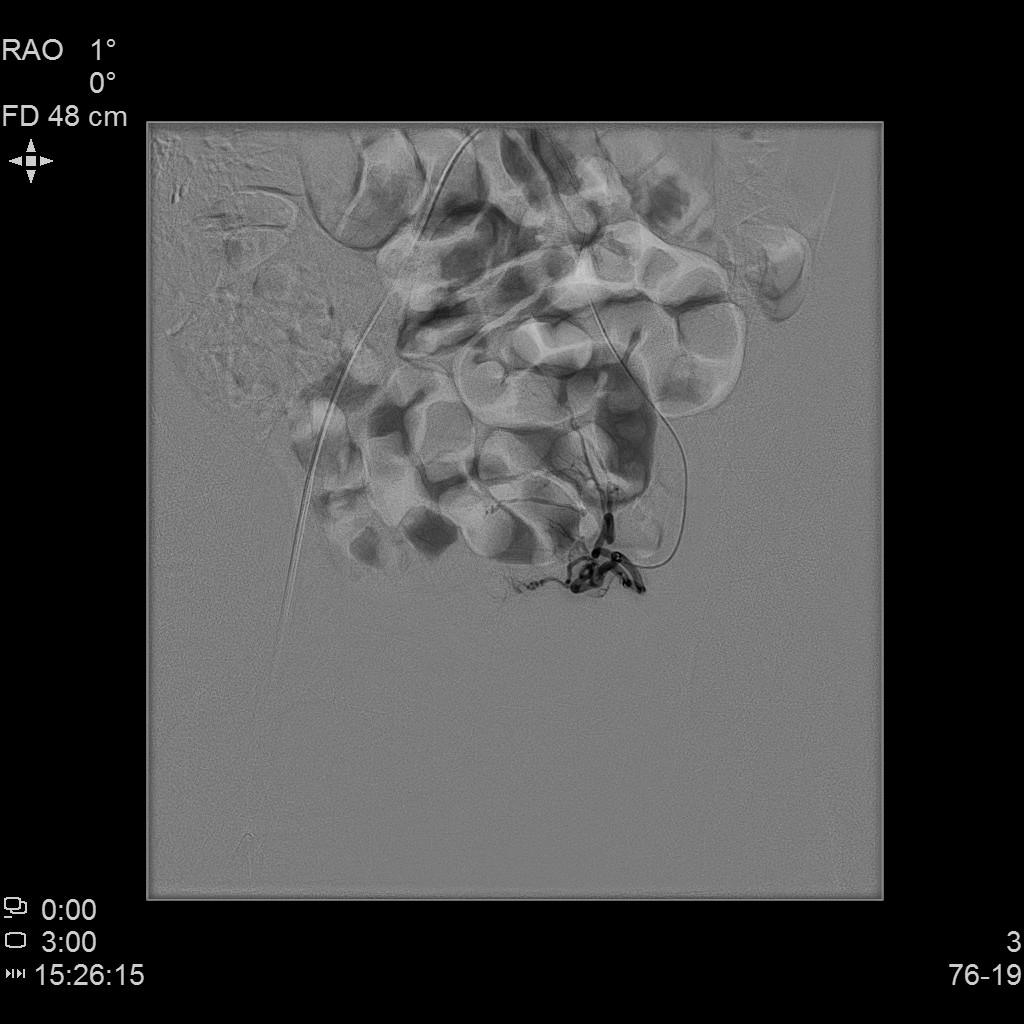

- 行子宫腺肌症介入栓塞治疗

- 插管至右侧髂内动脉造影,显示右侧子宫动脉

- 插管至右侧子宫动脉,显示子宫右侧病灶情况

- 插管至左侧子宫动脉,显示子宫左侧病灶情况